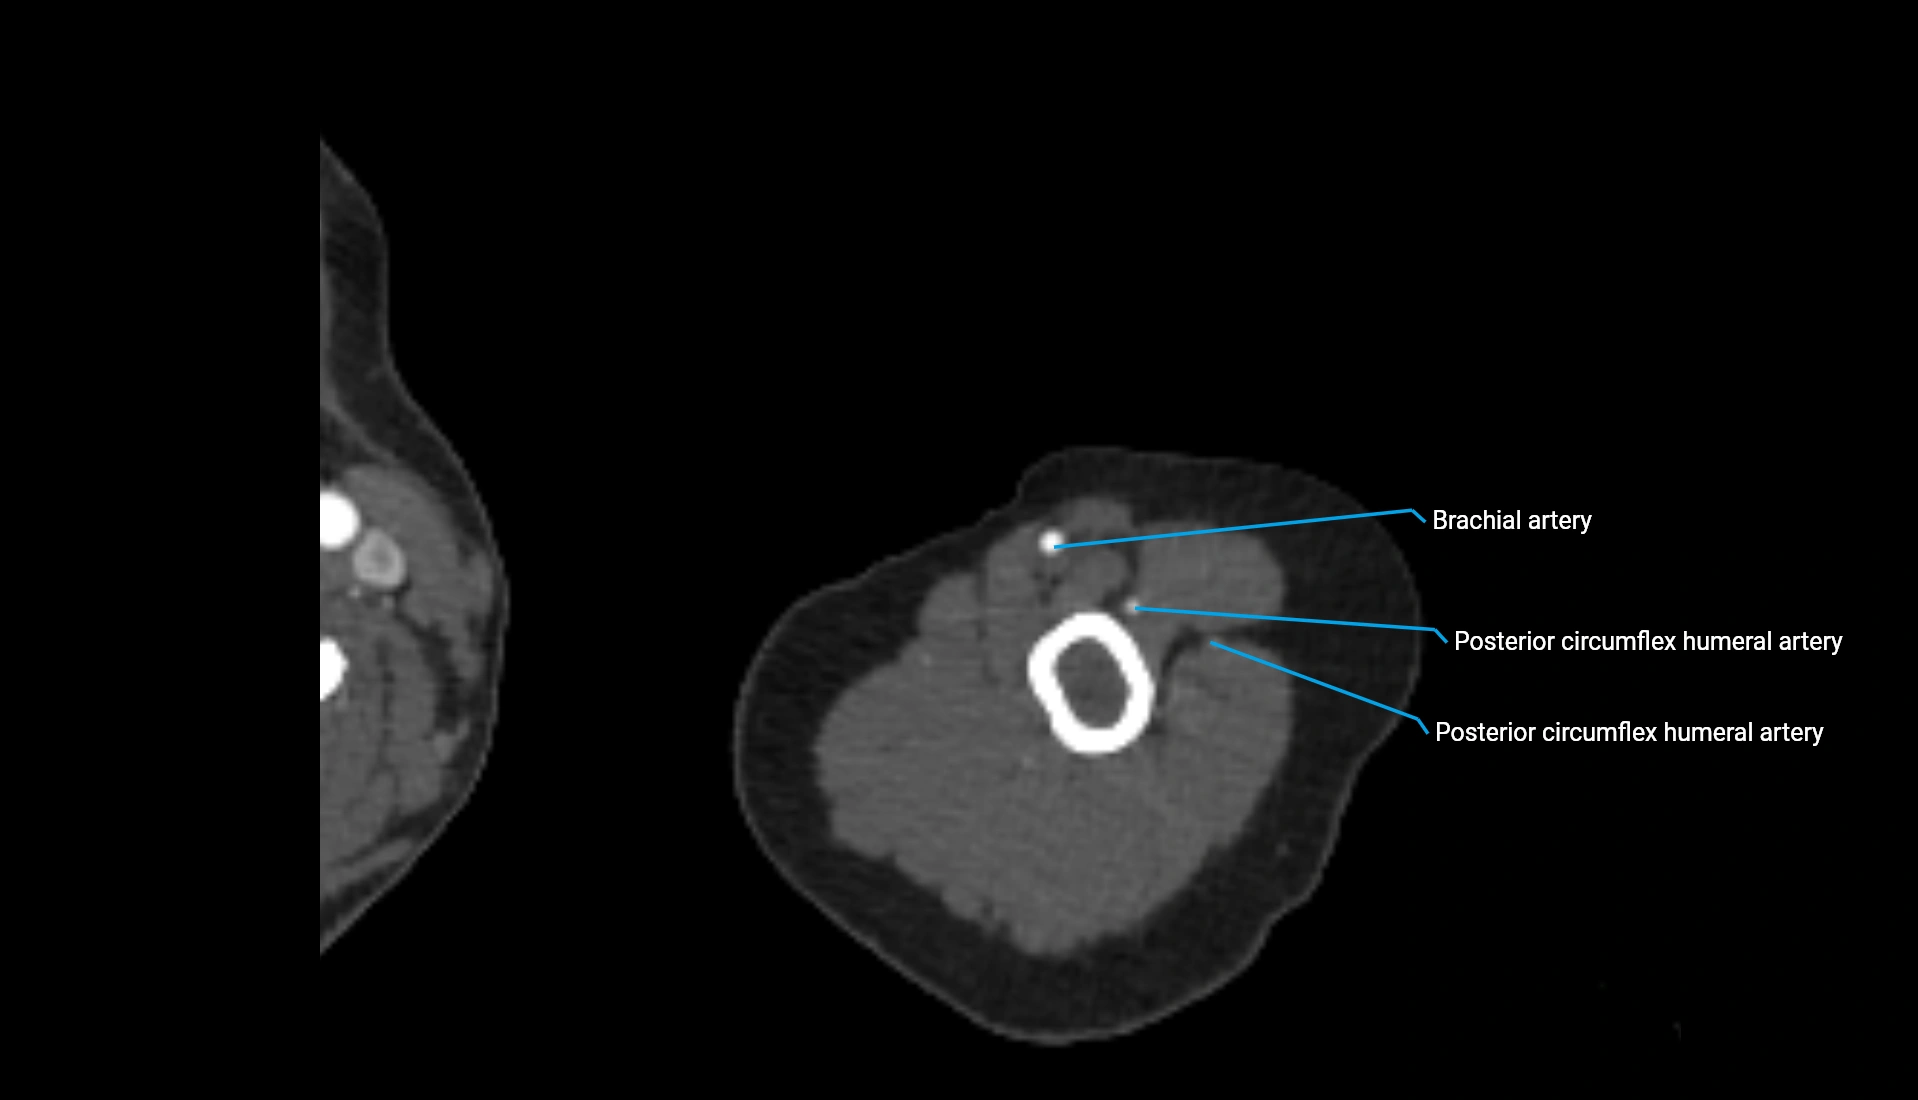

CT Appearance

Non-Contrast CT:

• Cortex: High-density, sharply defined

• Subchondral bone: Dense cancellous matrix

• Articular surface: Smooth concave contour articulating with the capitellum

• Excellent for evaluating bone integrity, alignment, and subtle fractures